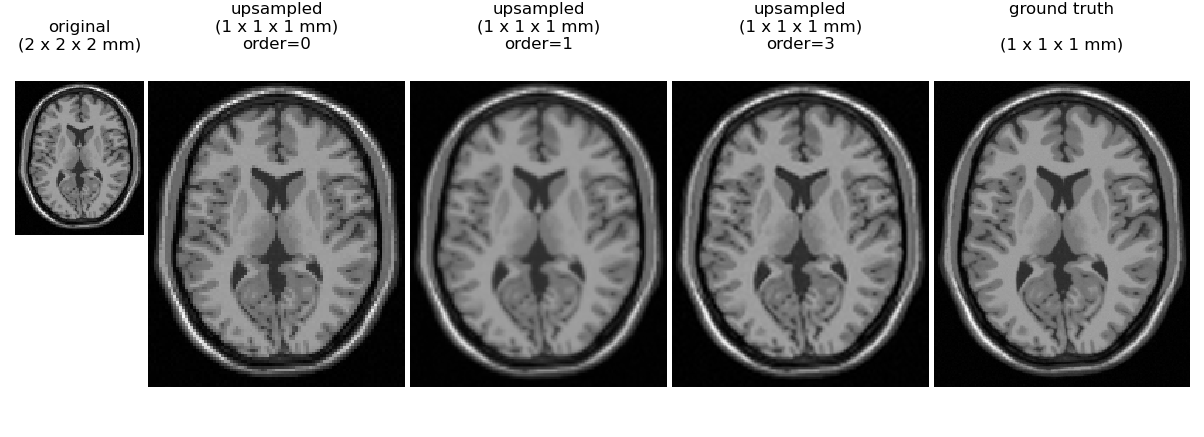

An illustration of interpolation order is given for a synthetic brain MRI (only one axial slice of the 3D brain is displayed). At the left is a simulated volume at 2 mm resolution. We then use scipy.ndimage.zoom to upsample the volume by a factor fo 2.0 along all axes to give an interpolated image where each voxel is of size 1 x 1 x 1 mm.

Here we can see that nearest neighbor (order=0) gives a blocky appearance, while order=1 (trilinear interpolation) also has some loss of detail relative to order 3 spline interoplation. No interpolation method can perfectly recover the true 1 mm simulated image shown on the right, indicating that one cannot rely on interpolation alone as a method to reduce MRI exam time without a sacrifice in image quality.